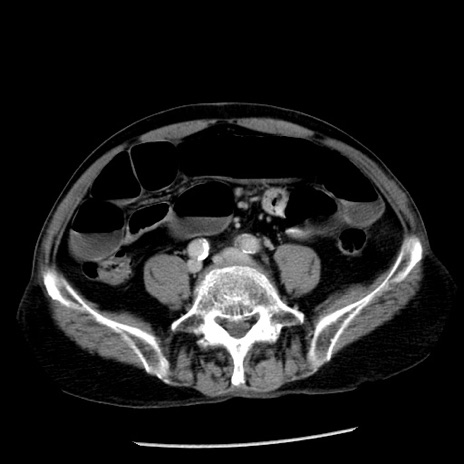

症例26(横断像)

【症例】80歳代男性

【主訴】嘔吐

【現病歴】昨晩2回嘔吐あり、今朝になっても嘔吐あり。来院。

【既往歴】胃潰瘍

【身体所見】意識清明、BT 37.6℃、BP 166/95mmHg、HR 100bpm、SpO2 97%、腹部:平坦・軟、腸蠕動音聴取良好、圧痛なし。

【データ】WBC 21900、CRP 1.46